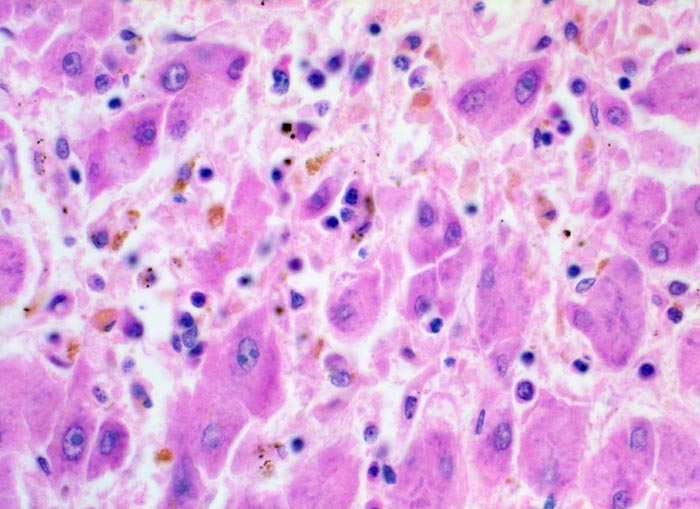

Das histologische Bild der akuten Hepatitis vom Virustyp ist gekennzeichnet durch eine lobuläre Entzündung bei fehlender portaler Fibrose und nur geringer entzündlicher Infiltration der Portalfelder. Es finden sich ballonierte Hepatozyten, Apoptosen ( 1164) und fleckige Nekrosen. Perivenuläre Nekrosen, Brückennekrosen oder konfluierende multilobuläre Nekrosen und eine läppchenzentrale Cholestase können vor allem in klinisch fulminant verlaufenden Fällen nachgewiesen werden. Zahlreiche Makrophagen, welche Diastase-PAS positives Zeroidpigment ( 4319) von phagozytierten nekrotischen Hepatozyten enthalten, zeugen im subakuten Stadium von einer abgelaufenen akuten Hepatitis mit Parenchymnekrosen. Eine Unterscheidung der verschiedenen Typen der viralen Hepatitis und einiger Formen medikamentöser Hepatitiden gelingt rein morphologisch aufgrund des unspezifischen Bildes meist nicht. Für eine ätiologische Klassifizierung sind zusätzliche klinische Angaben erforderlich (Anamnese, Medikamente, Serologie).